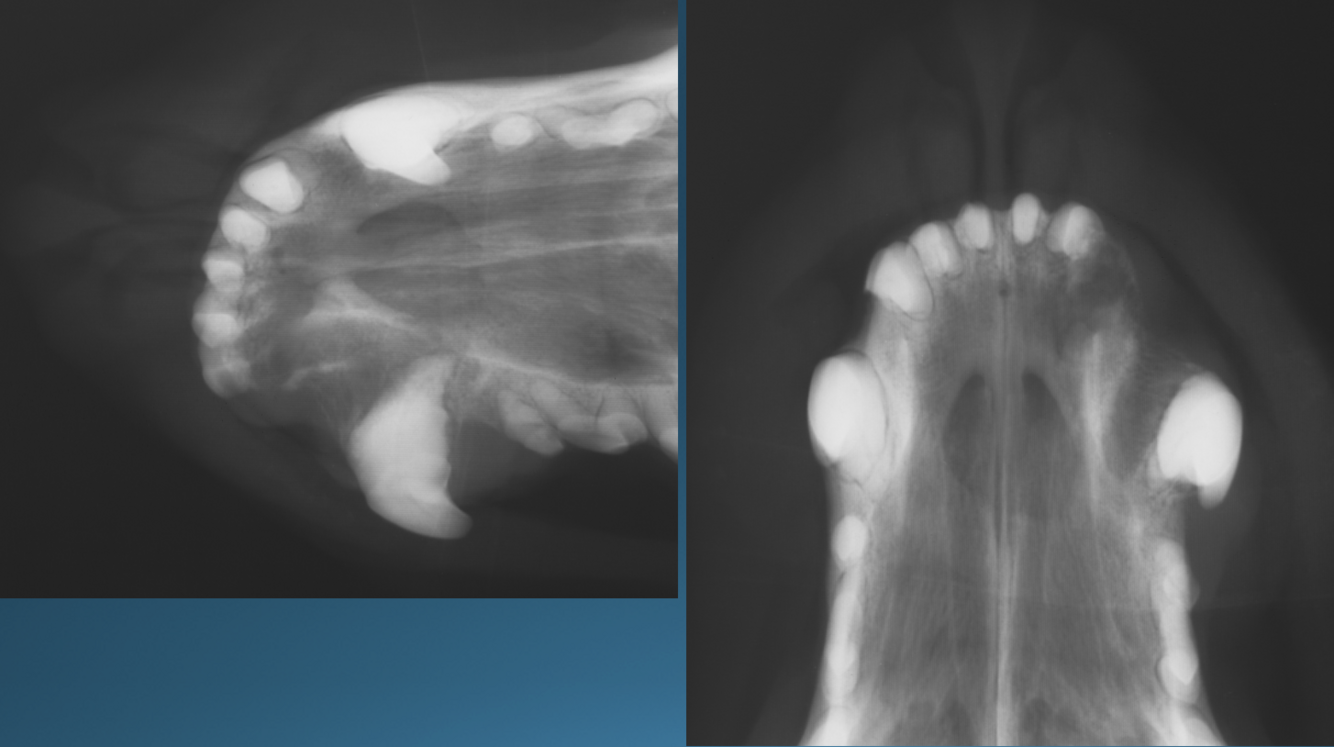

What is shown in these images?

A

Top Left and Right:

-hydrocephalus with doming of cranial vault

Bottom Left:

-normal

How well did you know this?